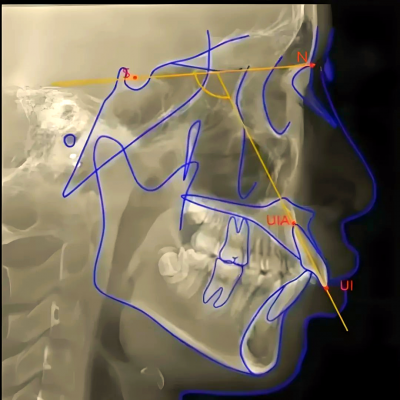

eSet学院新专栏上线!首批设计案例库14个典型案例设计辅导上线

eSet学院新专栏上线!首批设计案例库14个典型案例设计辅导上线 案例库链接:B站搜索“易美智汇”,选择合集和系列“eSet设计案例库” https://space.bilibili.com/1270...